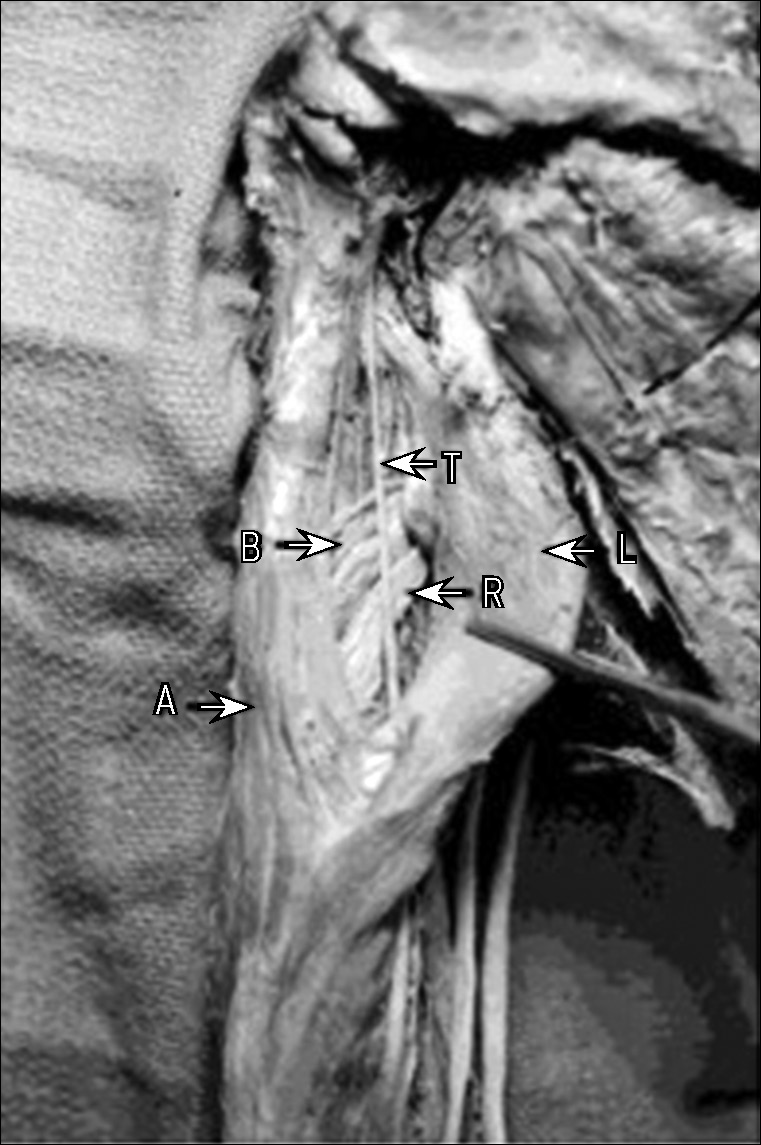

Рис. 1. Изображение задней поверхности проксимального отдела левого плеча, демонстрирующее проксимальное прикрепление сухожилия четвёртой головки трёхглавой мышцы плеча (T) по отношению к лучевому нерву (R), глубокой плечевой артерии (B), брюшку длинной головки (L) и латеральной головке трёхглавой мышцы плеча (A) [4].

Fig. 1. Photograph of the proximal aspect of the posterior compartment of the left arm demonstrating the proximal attachment of the fourth head of the triceps brachii tendon (T) in relation to the radial nerve (R), deep brachial artery (B), long head muscle belly (L) and lateral head muscle belly (A) [4].